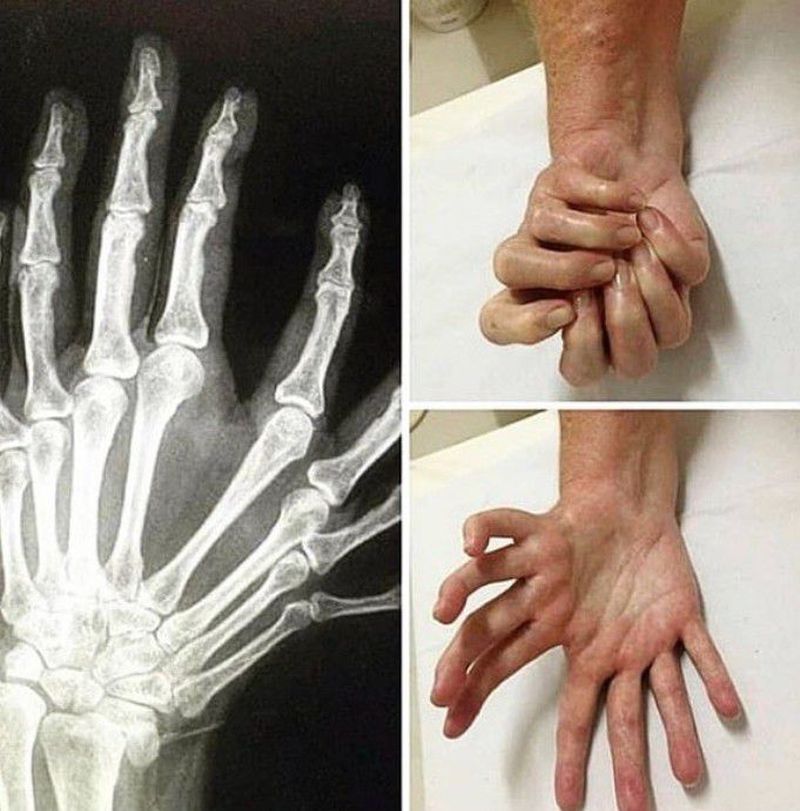

Polydactyly is one of the most common congenital hand deformities managed by orthopaedic surgeons. It is most often found in isolation; however, rarely, it may be associated with genetic syndromes. Polydactyly is classified as postaxial, preaxial, or central depending on the radioulnar location of the duplicated digits. Postaxial polydactyly, which affects the ulnar side of the hand, is most common and is typically managed with excision or suture ligation of the supernumerary digit. Preaxial polydactyly, which affects the thumb or radial side of the hand, often requires reconstructive techniques to ensure a functional, stable thumb. Central polydactyly is much less common, and reconstruction can be challenging.

Since the patient can make a fist I would say the extra fingers are functional

It seams the supernumerary digits would be useful...piano comes to mind, however the psychosocial effects could be devastating as people would react agast, like denelle, with these anomalies. Sharing the reconstruction follow up would be appreciated. thanks for sharing.